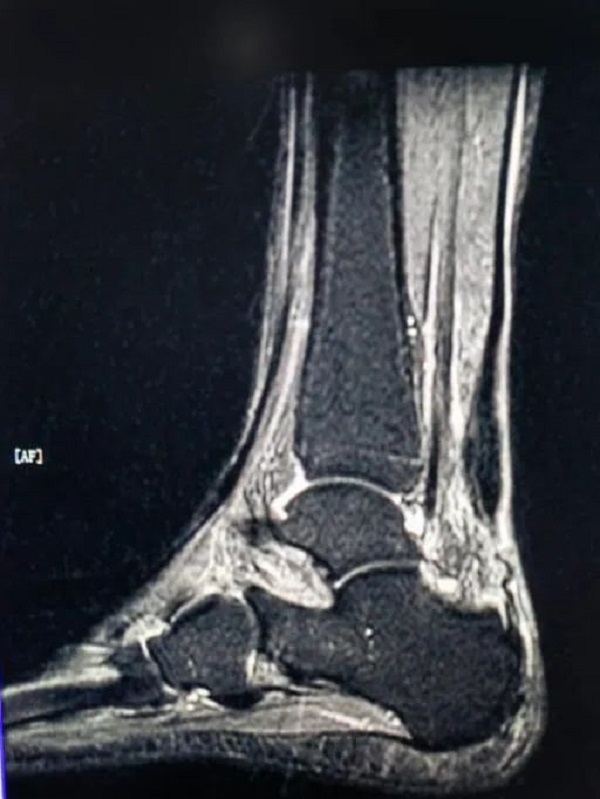

术前外观照,跟腱断端明显 术前MRI图像